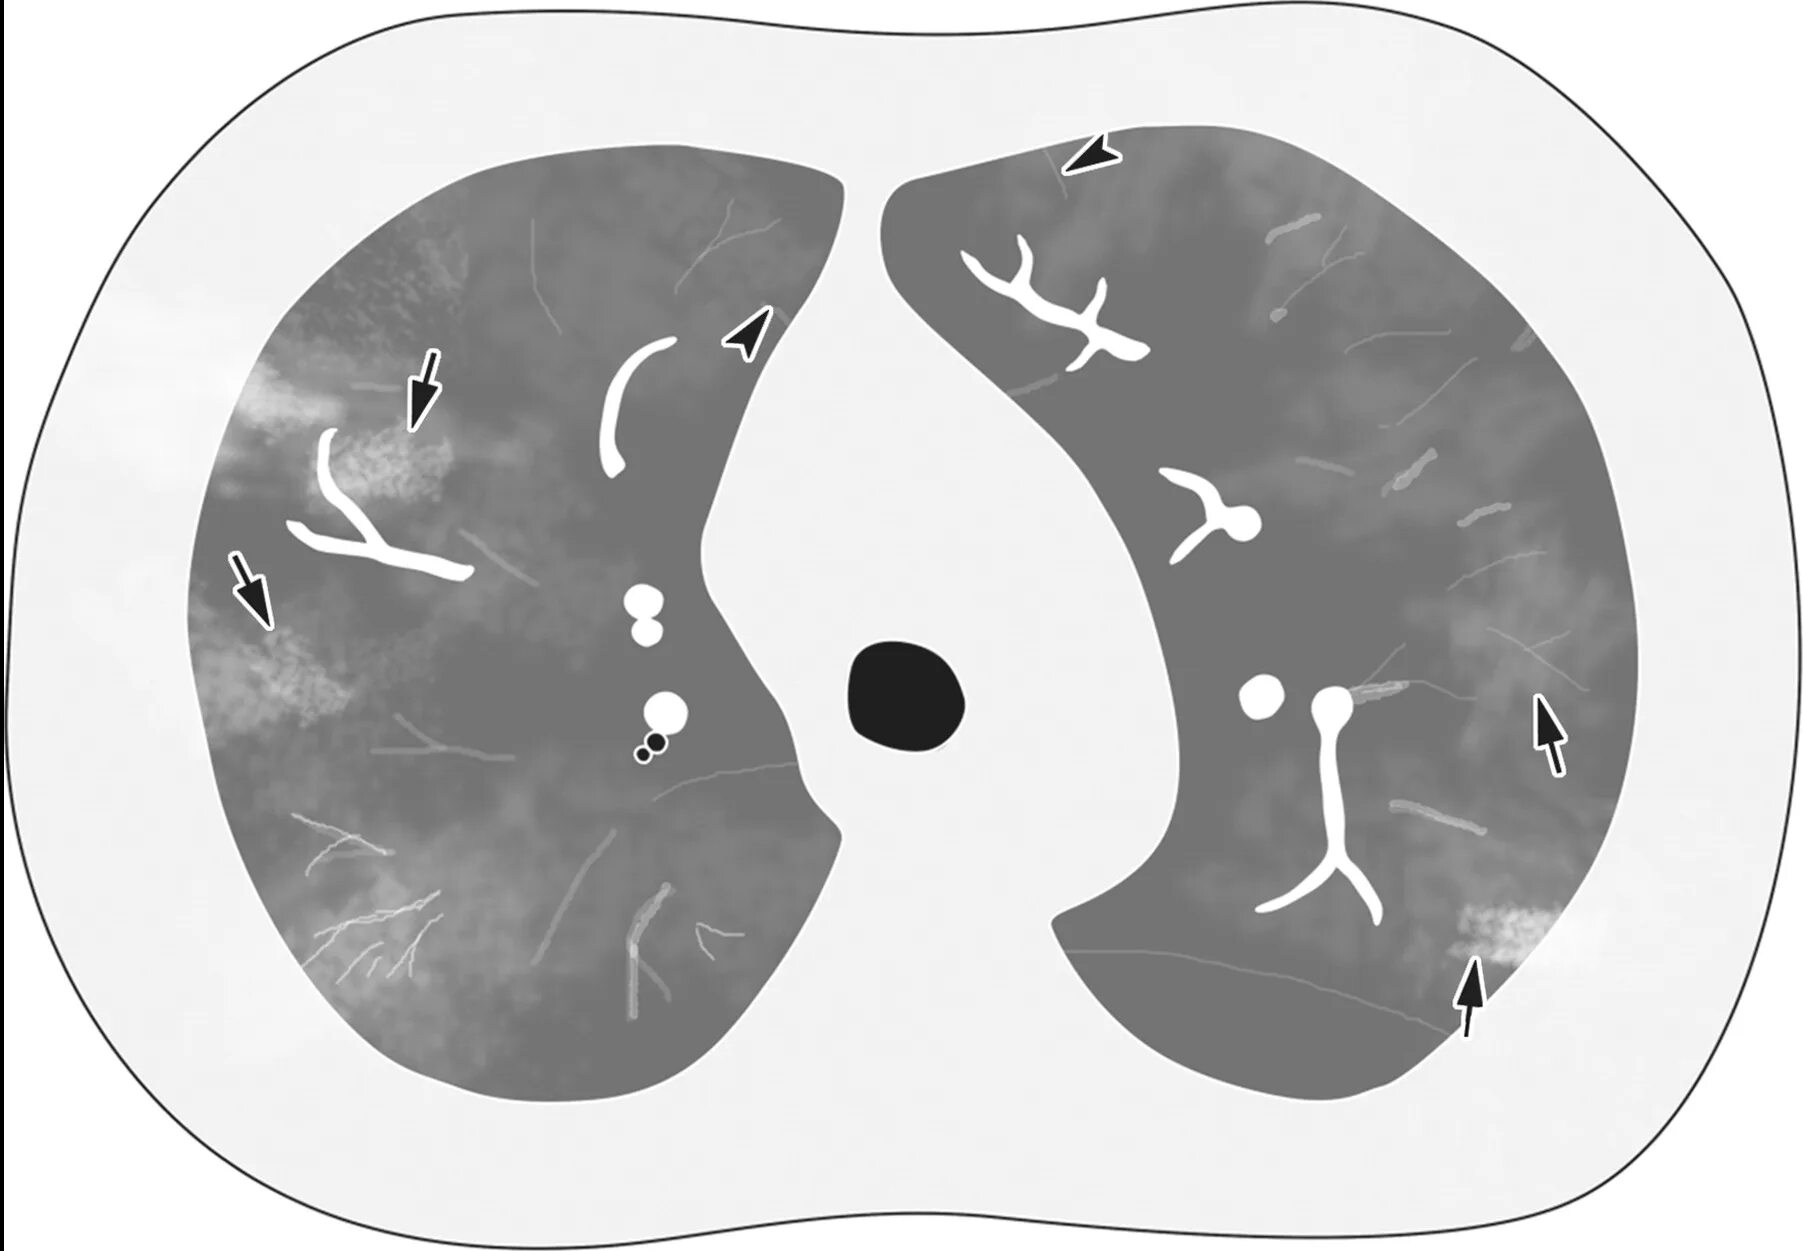

Мозаичная перфузия